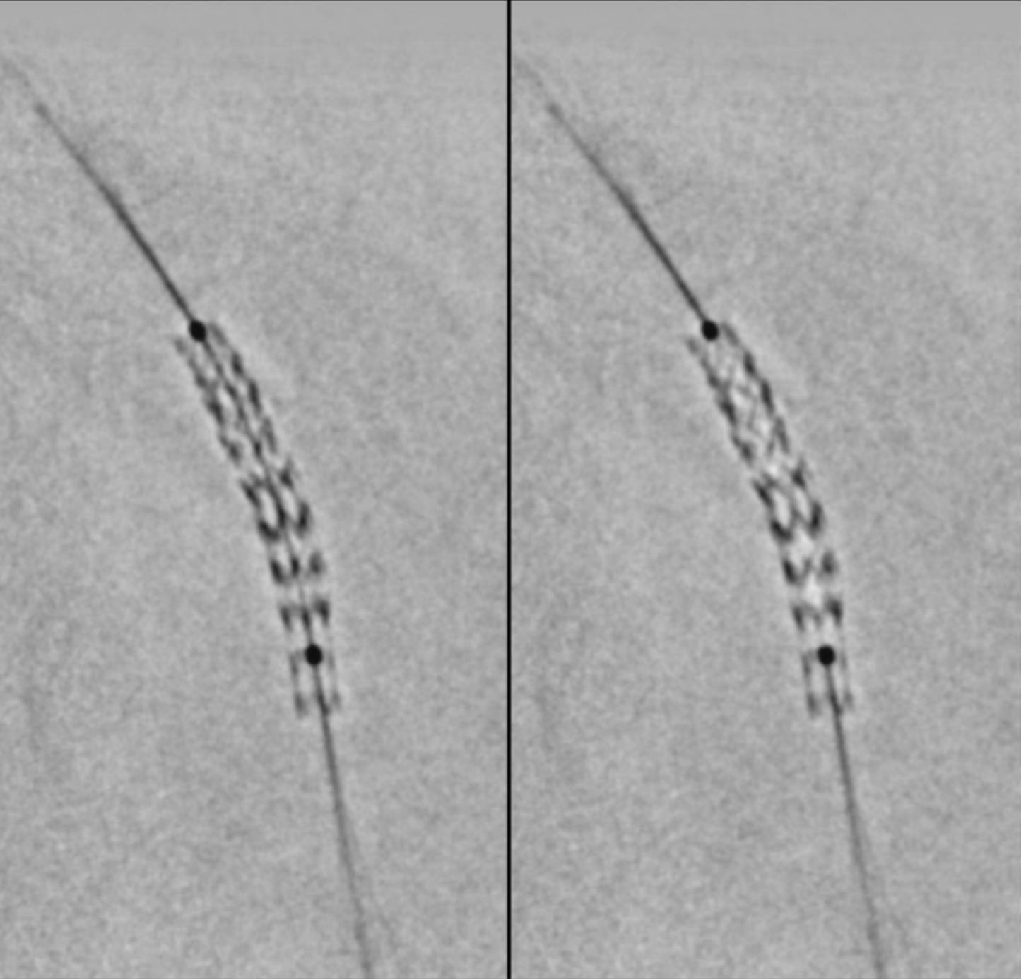

Stent Boost Please !

During this procedure, we performed a Digital image enhancement revealing: